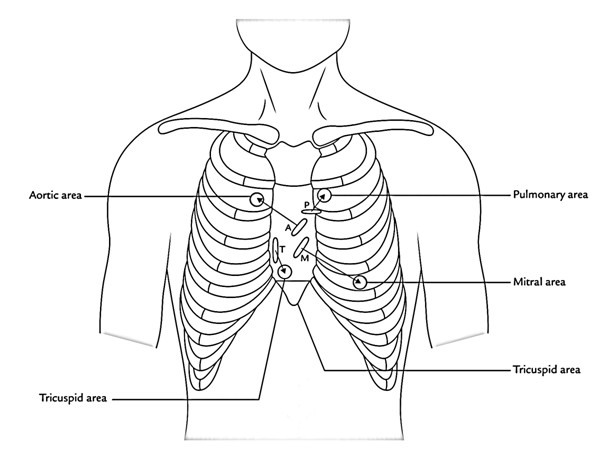

B the relevant anatomy shown from the front view. The tricuspid valve lies between the right atrium and the right ventricle and is placed in a more apical position than the mitral valve. The tricuspid valve has an area of 4 to 6 cm square and is located between the right atrium and the right ventricle of the heart.

Auscultating Heart Soundsin The Following Procedure Yo

Auscultating Heart Soundsin The Following Procedure Yo

Surface Markings Of The Cardiac Valves And Auscultatory

Surface Markings Of The Cardiac Valves And Auscultatory